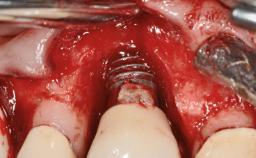

In 2004, the patient, a smoker, began dental treatment at the ACTA graduate clinic. She was a TV producer exposed to a lot of stress in her job and had a sick husband. Her maxillary teeth had been extracted, as had the mandibular canines, premolars, and molars, with the exception of tooth 34. She received a complete maxillary denture and a mandibular skeleton denture. In October 2007, her maxilla was augmented by an oral and maxillofacial surgeon; in March 2008, implants (Biomet 3i, Palm Beach, Florida, USA) were inserted at that same clinic. In 2008, the patient was presented at the Department of Oral Implantology and Prosthetic Dentistry to request restorations for her implants. An implant-supported overdenture was planned. She also asked if we could restore her occlusion with fixed prosthetics.

| Bone Volume | Deficient horizontally, requiring prior grafting |